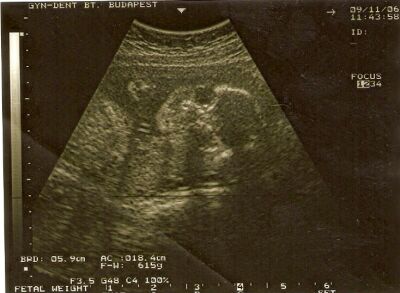

Képzeljétek, nálunk a cukros vérvétel 3 vizsgálatból áll. Egyik nap leveszik, és megnézik, normál értékű-e. Ha már ekkor gáz van, akkor nincs terheléses. Ha ok, akkor mehetsz másnap mindkettőre. Ezzel a jövő hétfő-keddi reggeli programomat meg is oldották...

Szülésznő: nem tudom, máshol hogy megy, a Szent Imrében időben kell lépni (24-30 hét), mert később már "elkelnek" a szülésznők. Én hiszem, hogy jó dolog, sőt, egy normális lefolyású szülésnél több szerepe és feladata van, mint a dokinak. Én választottam, mert gátvédelemmel szeretnék szülni, és az ugye csak folyamatos kontrollal megy. Persze, ha aznap épp ügyeletes, ki tudja mi van. Vagy talán beugranak egymás helyett?? A fogadott szülésznő szokott hátat masszírozni fájdalomcsillapításként, homeopátiás szereket adni, stb. De az biztos, hogy ehhez a szakmához hihetetlen elhivatottság kell, úgyhogy szerintem az is biztonságban érezheti magát, aki nem él a választás lehetőégével.